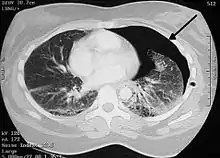

![]() تبين الأشعة السينية للصدر وجود استرواح الصدر على اليمين (يسار الصورة)، حيث تبين أيضًا غياب علامات الرئة لوجود هواء حر داخل الصدر. A large right-sided spontaneous pneumothorax (left in the image). An arrow indicates the edge of the collapsed lung | |

الأشعة السينية على الصدر

عادة ما يكون التصوير الشعاعي العادي للصدر، بإشعاع الأشعة السينية من الخلف (من الخلف للأمام) هو أنسب فحص في البداية. وعادة ما يتم تنفيذ ذلك خلال الشهيق (مع كتم النَفَس). لأن التصوير بالأشعة السينية أثناء الزفير (بعد خروج الهواء) لا يعطي أي معلومات إضافية.[12][13] إذا لم تُظهر الأشعة السينية الساقطة من الخلف للأمام استرواح صدري، ولكن كان هناك شكوك قوية في وجوده، يتم عمل أشعة سينية جانبية ( بإسقاط الأشعة من الجانب)، ولكن هذه ليست الطريقة الروتينية.[13][17] ومن المألوف وجود انحراف المنصف (التركيب بين الرئتين التي يحتوي على القلب، والأوعية الدموية الكبيرة، والممرات الهوائية الكبيرة) بعيدا عن الرئة المتضررة بسبب اختلافات الضغط. لذا فإن هذا الانحراف ليس دليلا على حدوث استرواح الصدر الضاغط، إنما يتحدد أساسا عن طريق مجموعة من الأعراض بالإضافة إلى نقص الأكسجين، والصدمة.[12]

يمكن تحديد حجم استرواح الصدر (أي حجم الهواء في الفضاء الجنبي) بدرجة معقولة من الدقة عن طريق قياس المسافة بين جدار الصدر والرئة، ويتم على أساسه تحديد العلاج، لأنه يتم التعامل مع وجود استرواح صدري أصغر بشكل مختلف. وجود طبقة رقيقة من الهواء حجمها 2 سم يعني أن استرواح الصدر يحتل حوالي 50٪ من نصف الصدر.[13] وقد ذكرت المبادئ التوجيهية المهنية البريطانية أن القياس يجب أن يتم على مستوى باب الرئة (مكان دخول الأوعية الدموية والمسالك الهوائية في الرئة) باعتبار 2سم كنقطة فاصلة،[13] في حين تنص المبادئ التوجيهية الأمريكية أن القياس ينبغي أن يتم من قمة الرئة مع التفريق بين استرواح الصدر "الصغير" و "الكبير" بفاصل 3سم.[23] ولكن قد تبالغ الطريقة الأخيرة في حجم استرواح الصدر إذا كان يقع أساسا في القمة، وهو أمر شائع.[13] الروابط بين طرق القياس المختلفة ضعيفة، ولكن هي أفضل الطرق المتاحة السهلة لتقدير حجم استرواح الصدر.[13][17] يمكن أن يساعد المسح المقطعي (انظر أدناه) في تحديد حجم استرواح الصدر بدقة أكبر، ولكن لا يوصى باستخدامه الروتيني مع هذه الحالات.[23]

ليس كل استرواح صدري مثل الآخر، فقد لا يشكل بعضها سوى تجويف من الهواء في مكان معين في الصدر فقط.[13] كما يمكن ملاحظة كميات صغيرة من السوائل في الأشعة السينية على الصدر (استرواح الصدر الموهي)، وقد يكون هذا السائل دم.[12] في بعض الحالات، قد يكون الشيء الوحيد غير الطبيعي في الأشعة هو "علامة التلم العميق"، التي تظهر فيها المساحة الصغيرة الموجودة عادة بين جدار الصدر والحجاب الحاجز كبيرة بسبب الوجود غير الطبيعي للسوائل.[14]